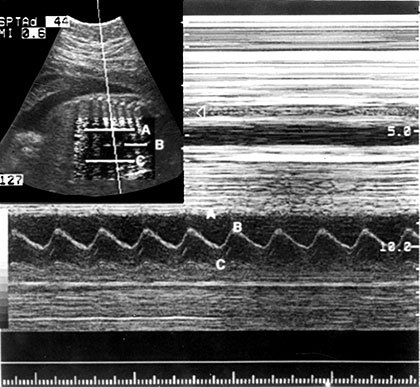

- M mode: If the series of B mode are displayed on a moving time base, the motion of mobile structure can be observed. This process forms the basis of echocardiography (Fig. 1.14).

Fig. 1.14: M-mode of display changes of echo amplitude and position with time. Display of changes in echo position is useful evaluation of rapidly moving structures such as cardiac valves and chamber walls. Here the three major moving structures in an M-mode image of fetal heart corresponds to the near ventricular wall (A) interventricular septum, (B) the far ventricular wall (C) the base line is a time scale and permits calculation of heart rate and M-mode data